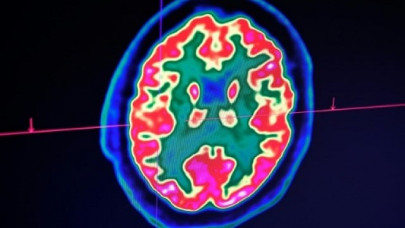

Confusion, seizure, strokes: How Covid-19 may affect the brain

A pattern is emerging among Covid-19 patients arriving at the hospitals